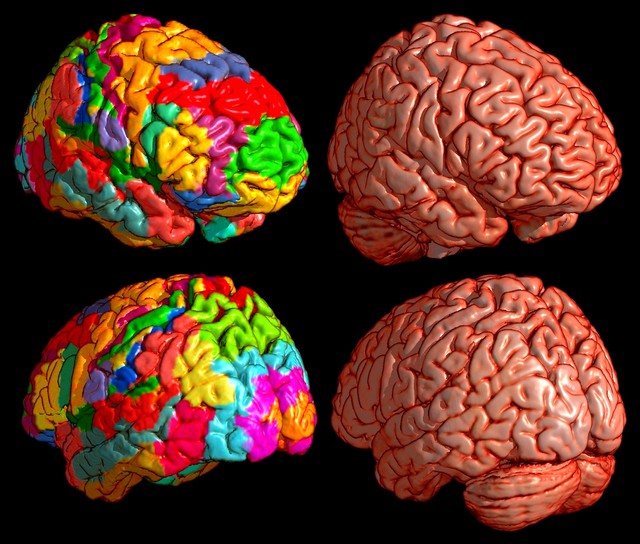

Коннектом мозга: визуализация связей и нейронных путей